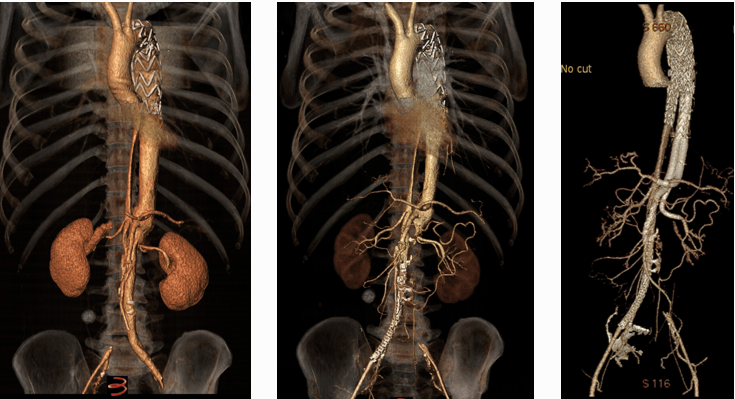

主动脉重塑差异与301分型

★ 术后转归差异

重塑差:假腔持续扩张,真腔受压(图文对照显示术后1年假腔未闭合)

重塑好:真腔恢复血流,假腔血栓化(影像显示术后1年假腔消失)

★ 301分型核心价值

分型依据:基于真/假腔与胸椎的空间关系(B1: 真腔贴椎体;B2: 螺旋混合;B3: 假腔贴椎体)

预后关联:

① B3型24个月胸主动脉扩张风险最高(42%,HR=13.91 vs B1型参照)

② B1型预后最佳(97%免于扩张)

意义:为TEVAR术后风险分层提供新工具(Mayo Clin Proc. 2020)